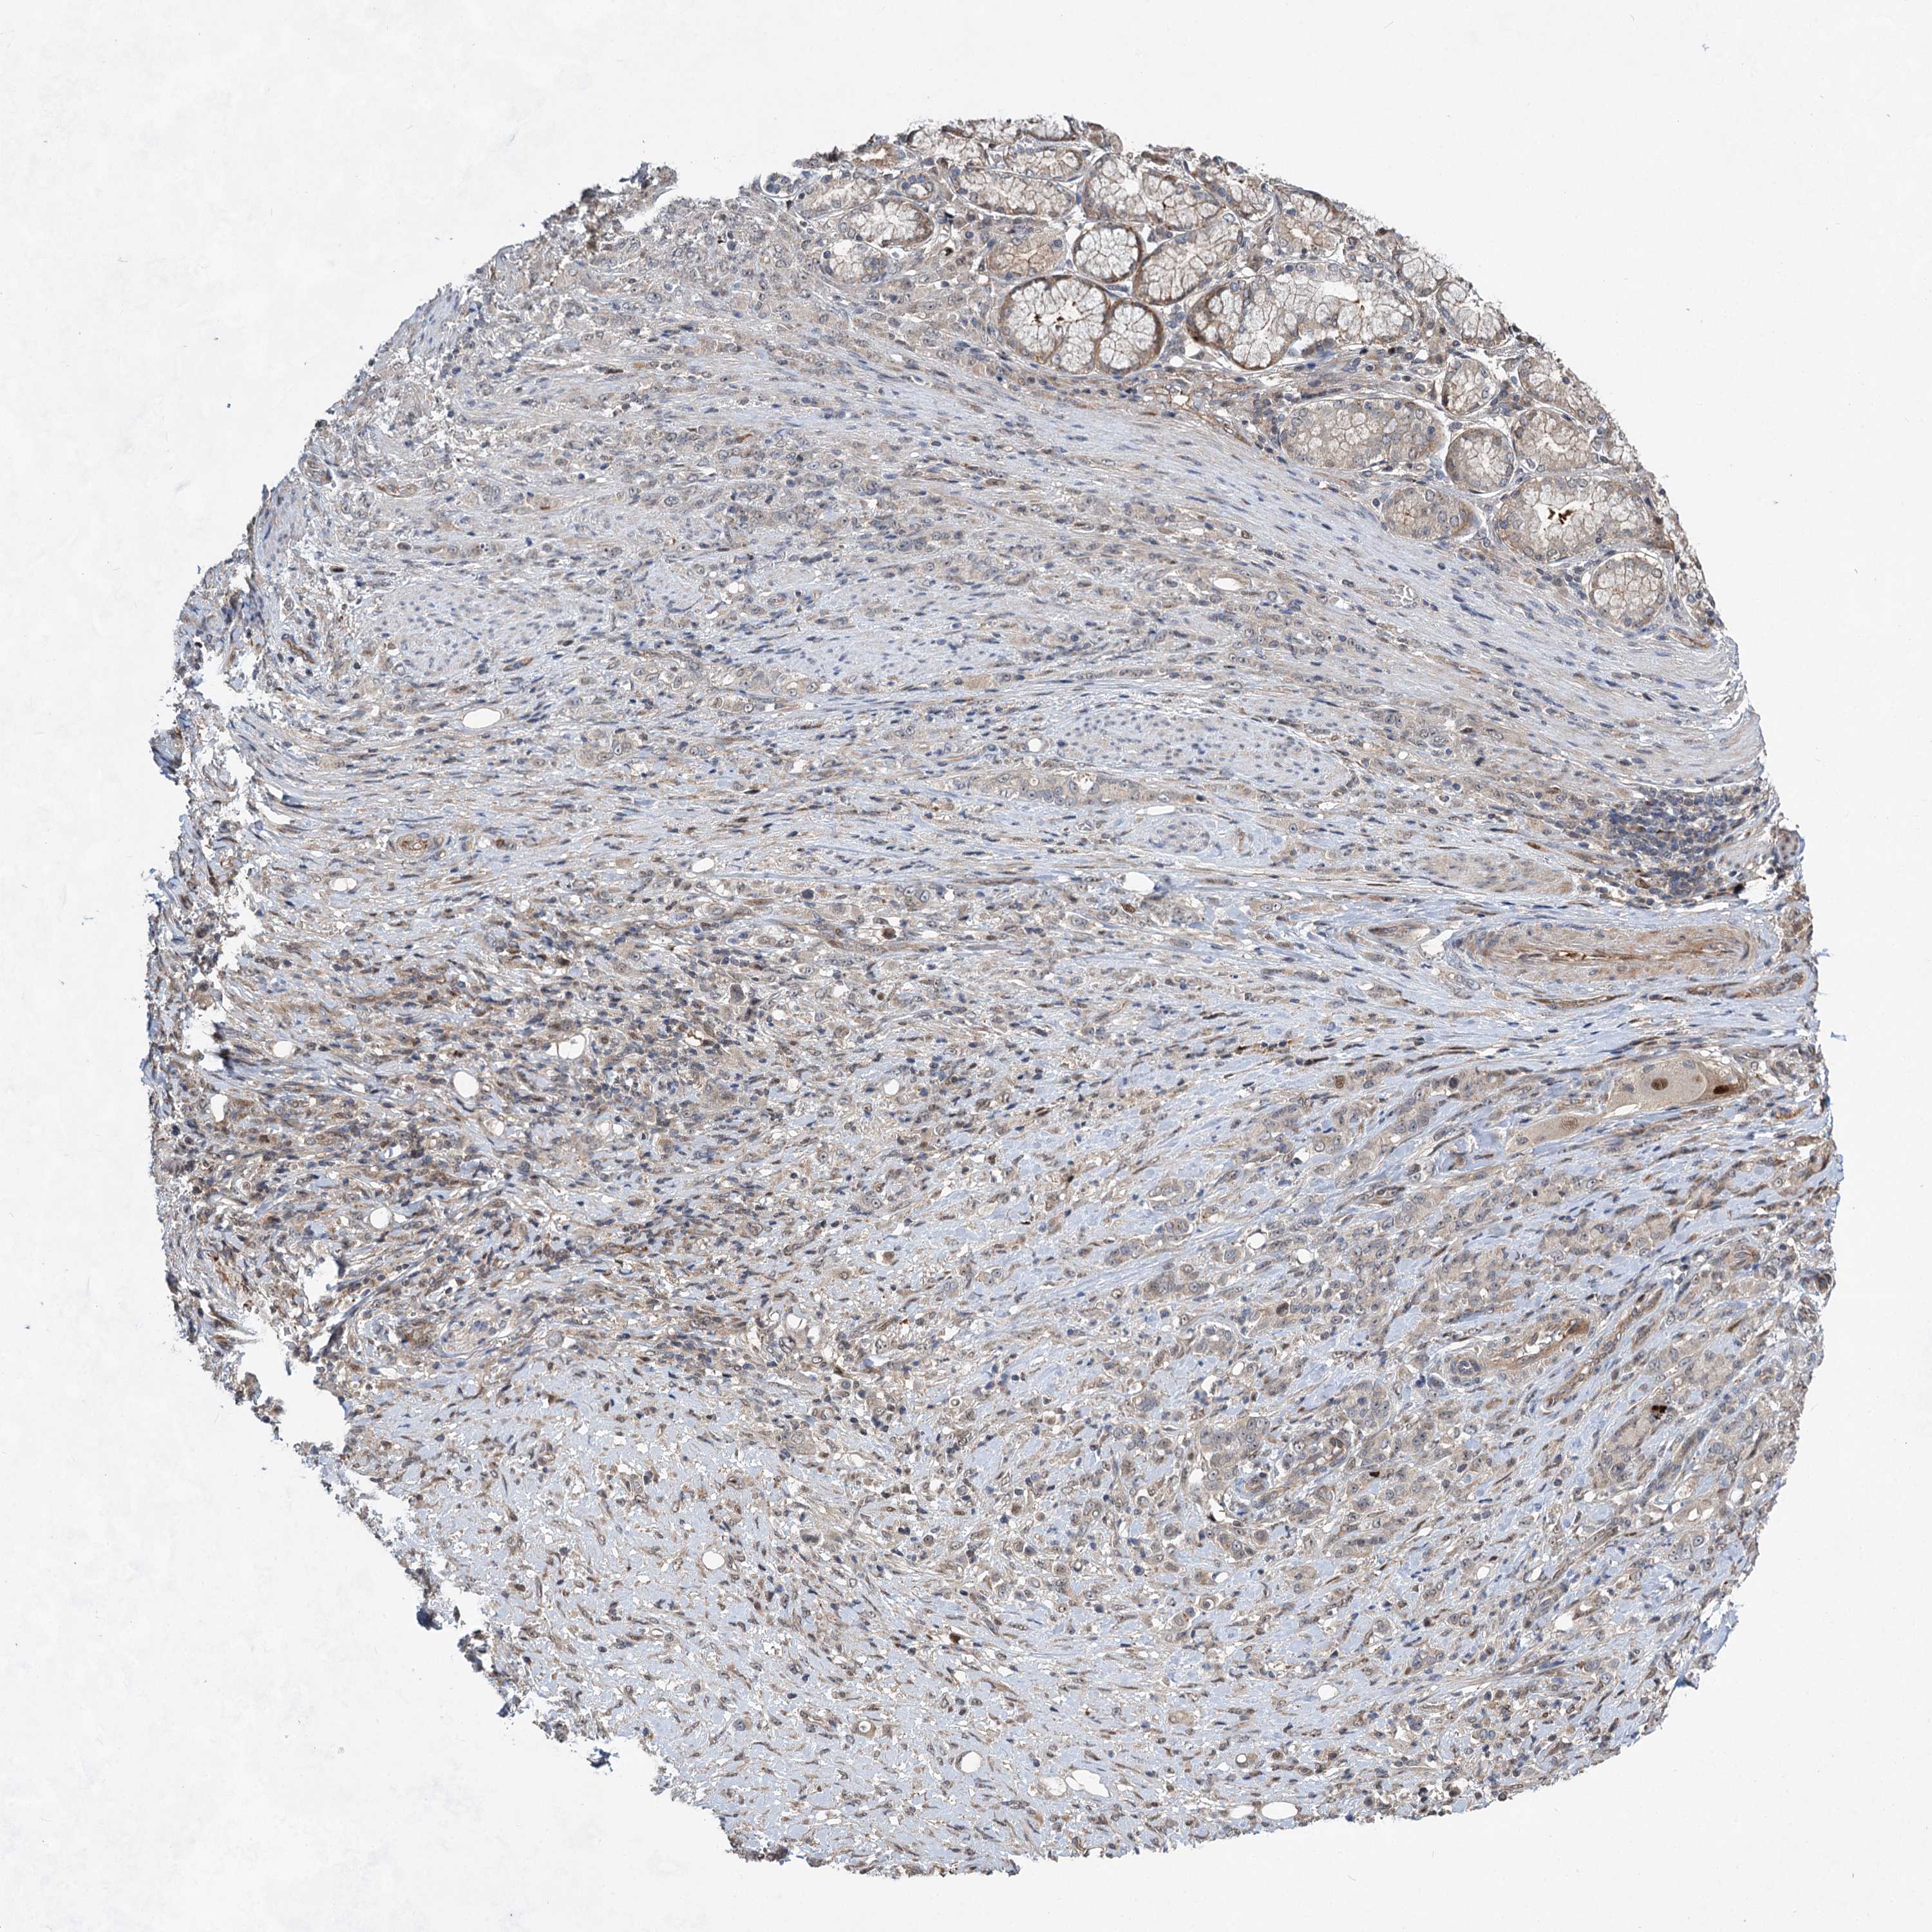

STOMACH CANCER - Protein expressioni

A mouse-over function shows sample information and annotation data. Click on an image to view it in a full screen mode. Samples can be filtered based on level of antibody staining by selecting one or several of the following categories: high, medium, low and not detected. The assay and annotation is described here.

Antibody stainingi

Antibody staining in the annotated cell types in the current human tissue is reported as not detected, low, medium, or high, based on conventional immunohistochemistry profiling in selected tissues. This score is based on the combination of the staining intensity and fraction of stained cells.

Each image is clickable and will lead to virtual microscopy that enables deeper exploration of all samples and also displays staining intensity scores, fraction scores and subcellular localization as well as patient and tissue information for each sample.

Antibody HPA037773

Staining

High

Medium

Low

Not detected

Intensity

Strong

Moderate

Weak

Negative

Quantity

>75%

75%-25%

<25%

None

Location

Nuclear

Cytoplasmic/membranous

Cytoplasmic/membranous,nuclear

Adenocarcinoma, NOS

Adenocarcinoma, High grade